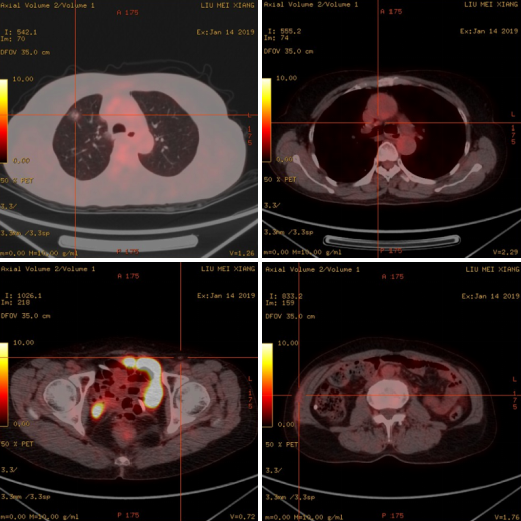

口服阿帕替尼第二个月,患者CA-125升高至87.5 U/ml(图4)。行PET-CT提示:1.右肺上叶磨玻璃影,部分代谢轻度增高,较前相仿,考虑为肿瘤性病变可能。2.阴道残端代谢无增高。3.腹膜后、双侧腋窝及双侧腹股沟区炎性或非特异性小淋巴结可能。4.右侧腰侧腹、右侧盆壁皮下片絮状影,代谢轻度升高,考虑炎性改变可能(图5)。结合病史,仍考虑为生化复发。为进一步延长PFI,给予患者口服替吉奥 50 mg,一天两次,连续14天,间隔7天。继续监测CA-125变化情况。

图5 患者生化复发后PET-CT结果